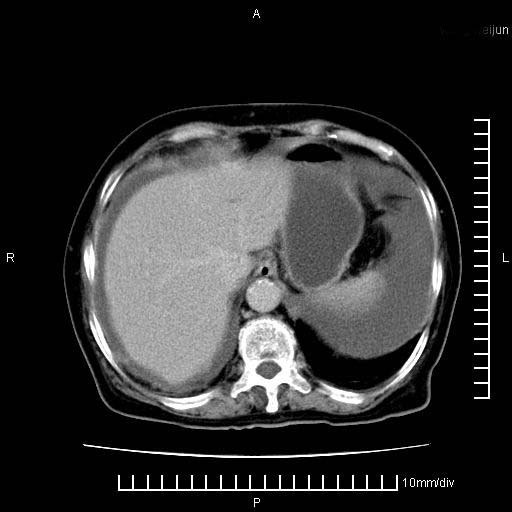

标题: CT28280:腹部增强:女性,80岁

上腹疼痛月余,外院核磁诊断胰腺癌。现临床示右下腹可明显触及包块,可片子上怎么没有看到?

1.胰腺颈体部癌。

2。腹腔积液。

3。右胸腔积液,伴右肺下叶部分萎陷。

4。右肾盂囊肿。

胰腺体部癌累及周围器官,腹膜、粘连

1。胰腺ca伴腹膜腔转移

2。肝左叶低密度灶,考虑转移可能

胰腺结构模糊,胰尾部见囊性包块,周围脂肪密度增高,左肾前筋膜增厚,胸水、腹水。不符合胰腺ca伴腹膜腔转移。考虑胰腺炎伴假性囊肿形成、胸腹腔积液。

右肾盂囊肿。